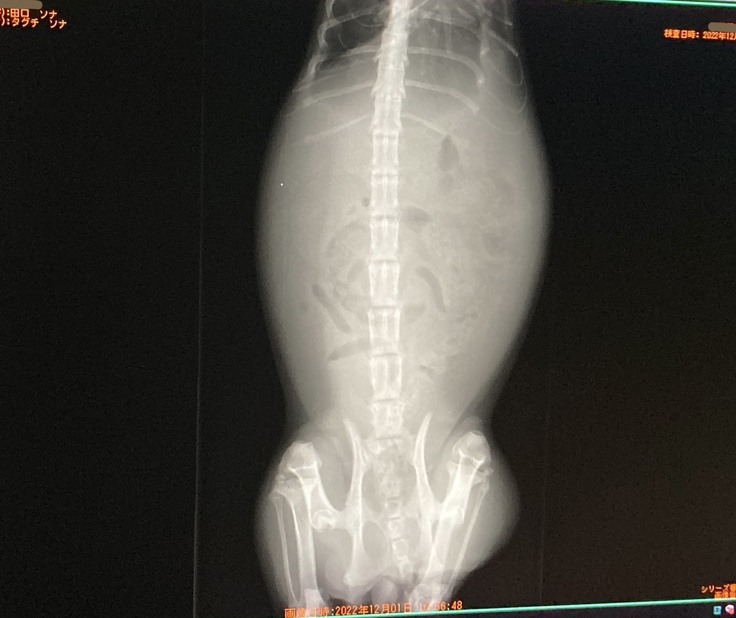

セカンドオピニオン病院 レントゲン結果↓(靄がかかった様に映るのは腹水だそうです)

ソナは腹水も溜まっていて、右腎臓の内側に2.5cm程の肉芽腫がある為、混合タイプでした。